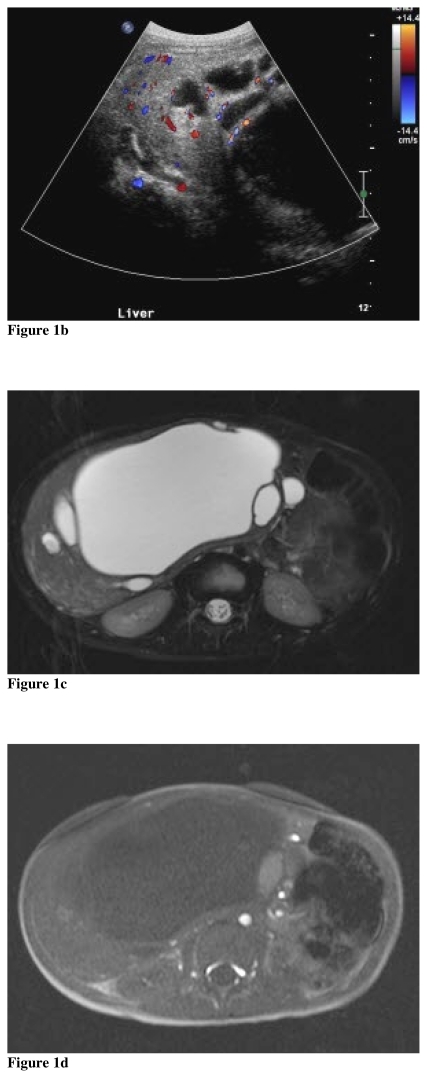

A 23-month-old male presented to his primary pediatrician with a six month history of increasing abdominal distention, progressively worsening vomiting, and weight loss. There was no history of fever or pain. On physical examination, hepatomegaly was present and the patient was referred for ultrasound (US). On songraphy, there was a large complex multilobulated cystic mass within the right liver. The largest cyst measured 16 × 10 × 12 cm. There were multiple smaller adjacent cysts with intervening internal septations measuring up to 5 mm in width (Fig. 1a). On color Doppler, vascularity was present in these septations (Fig. 1b). There was no vascularity within the cysts. To further assist in delineating the overall anatomy, magnetic resonance imaging (MRI) was performed.

Figure 1.

Mesenchymal cystic hamartoma in a 23-month-old male. (a) Transverse US image reveals a large complex cystic mass containing internal echos within the right liver lobe (b) transverse color US image at the inferior right liver demonstrates vascularity within septations (c) axial T2W MRI image with fat saturation (d) axial T1 pre and (e) post contrast demonstrates a multilobulated cystic mass within the right liver including one cyst - located just to the left of the dominant cyst - with internal hemorrhage. (f) gross pathological specimen. (g) disordered hepatic parenchyma with irregular bile ducts surrounded by immature mesenchyme, H&E 10X.

The patient was imaged on a 1.5T magnet (Siemens Magnetom SymphonyTM) utilizing the following sequences: 3 plane HASTE localizer sequences, axial T1 in and out of phase (TR 269/TE 4.7&2.3), coronal T1 gradient echo (TR 1676/TE 4.9), three plane T2 turbo spin echo (TR 5250/TE 154) with fat saturation, and three plane T1 (TR 884/TE 21) spin echo with fat saturation post contrast (Magnevist®, Bayer Healthcare). MRI demonstrated a very large complex cystic lesion occupying the entire right lobe of the liver resulting in mass effect on the adjacent organs including displacement of the left lobe of the liver. The mass measured 17 cm × 10 cm × 15 cm. The cystic areas were low in signal intensity on T1 and high signal intensity on T2 weighted sequences. There was a single cyst with high signal intensity on both T1 and T2 sequences located in the right anterior liver, highly suggestive of prior hemorrhage (Fig. 1c, 1d). The internal septations and rim of soft tissue surrounding the cysts enhanced post-contrast (Fig. 1e). There were no additional lesions identified in the liver. There was no adenopathy in the abdomen. The imaging findings were highly suggestive of benign mesenchymal cystic hamartoma. A right hepatic lobectomy was performed and this diagnosis was confirmed (Fig. 1f).